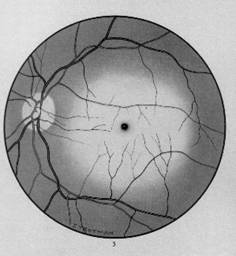

stadiu II - ingustarea calibrului la incrucisare si devierea vasului in baioneta cu dilatarea acestuia, in amonte de incrucisare (Fig. 17.2);

stadiu III (stadiu de pretromboza) - aparitia de mici hemoragii la nivelul zonei de incrucisare.

Fig. 17.2 - Angioscleroza retiniana hipertensiva